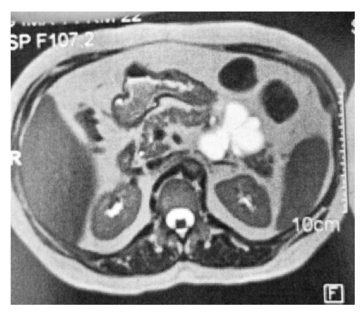

Um homem de 52 anos de idade apresenta a lesão pancreática assintomática mostrada a seguir.

Com base nesse caso hipotético, é correto afirmar que a lesão menos provável com relação ao diagnóstico final é o(a)